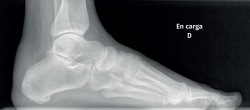

Son de elección las proyecciones dorsoplantar y sagital de ambos pies en carga, así como posteroanterior de tobillos en carga.

La radiografía simple en carga es la herramienta diagnóstica imprescindible de inicio(20). Permite valorar alineaciones, dismetrías, medir ángulos, determinar la morfología del calcáneo y su tuberosidad posterior, caracterizar exostosis óseas, aumentos de grosor en las partes blandas retrocalcáneas y planificar gestos quirúrgicos (Figura 3).

Figura 3. Radiografía simple. Proyección sagital en carga. Calcificaciones moderadas en la inserción del tendón de Aquiles con entesofito intratendinoso. Alteraciones morfológicas tuberosidad posterior del calcáneo.